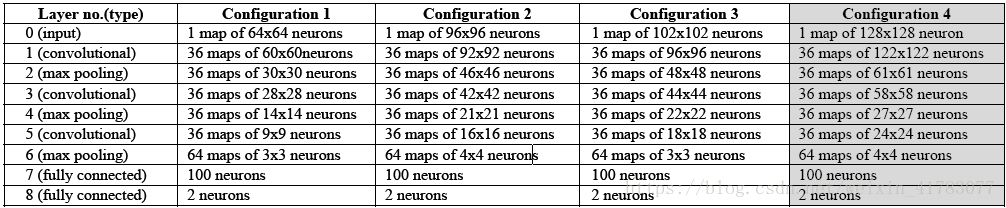

文献[34]提出了一种使用卷积神经网络实现在X射线图像中骨骼结构分割的方法,文献采用四种卷积神经网络模型提取图像特征,四种不同配置如表1所示,并在最后一层用softmax分类器对像素进行二分类,将骨骼区域从周围组织中分割出来。由于X射线图像的分辨率很高,为了减少训练的时间,选取局部感兴趣的区域进行训练。在分割的过程中,再不需要人为干涉,避免了人为选取特征存在误操作的风险。骨骼分割结果如图12所示,实验结果表明,第四种神经网络模型在像素误差(Pixel error)、兰德误差(Rand error)和分裂合并翘曲误差(Warping error)三个指标上均取得了优良的性能,如表2所示。

表1 四种卷积神经网络模型的配置

表2 四种卷积神经网络模型的性能和训练时间